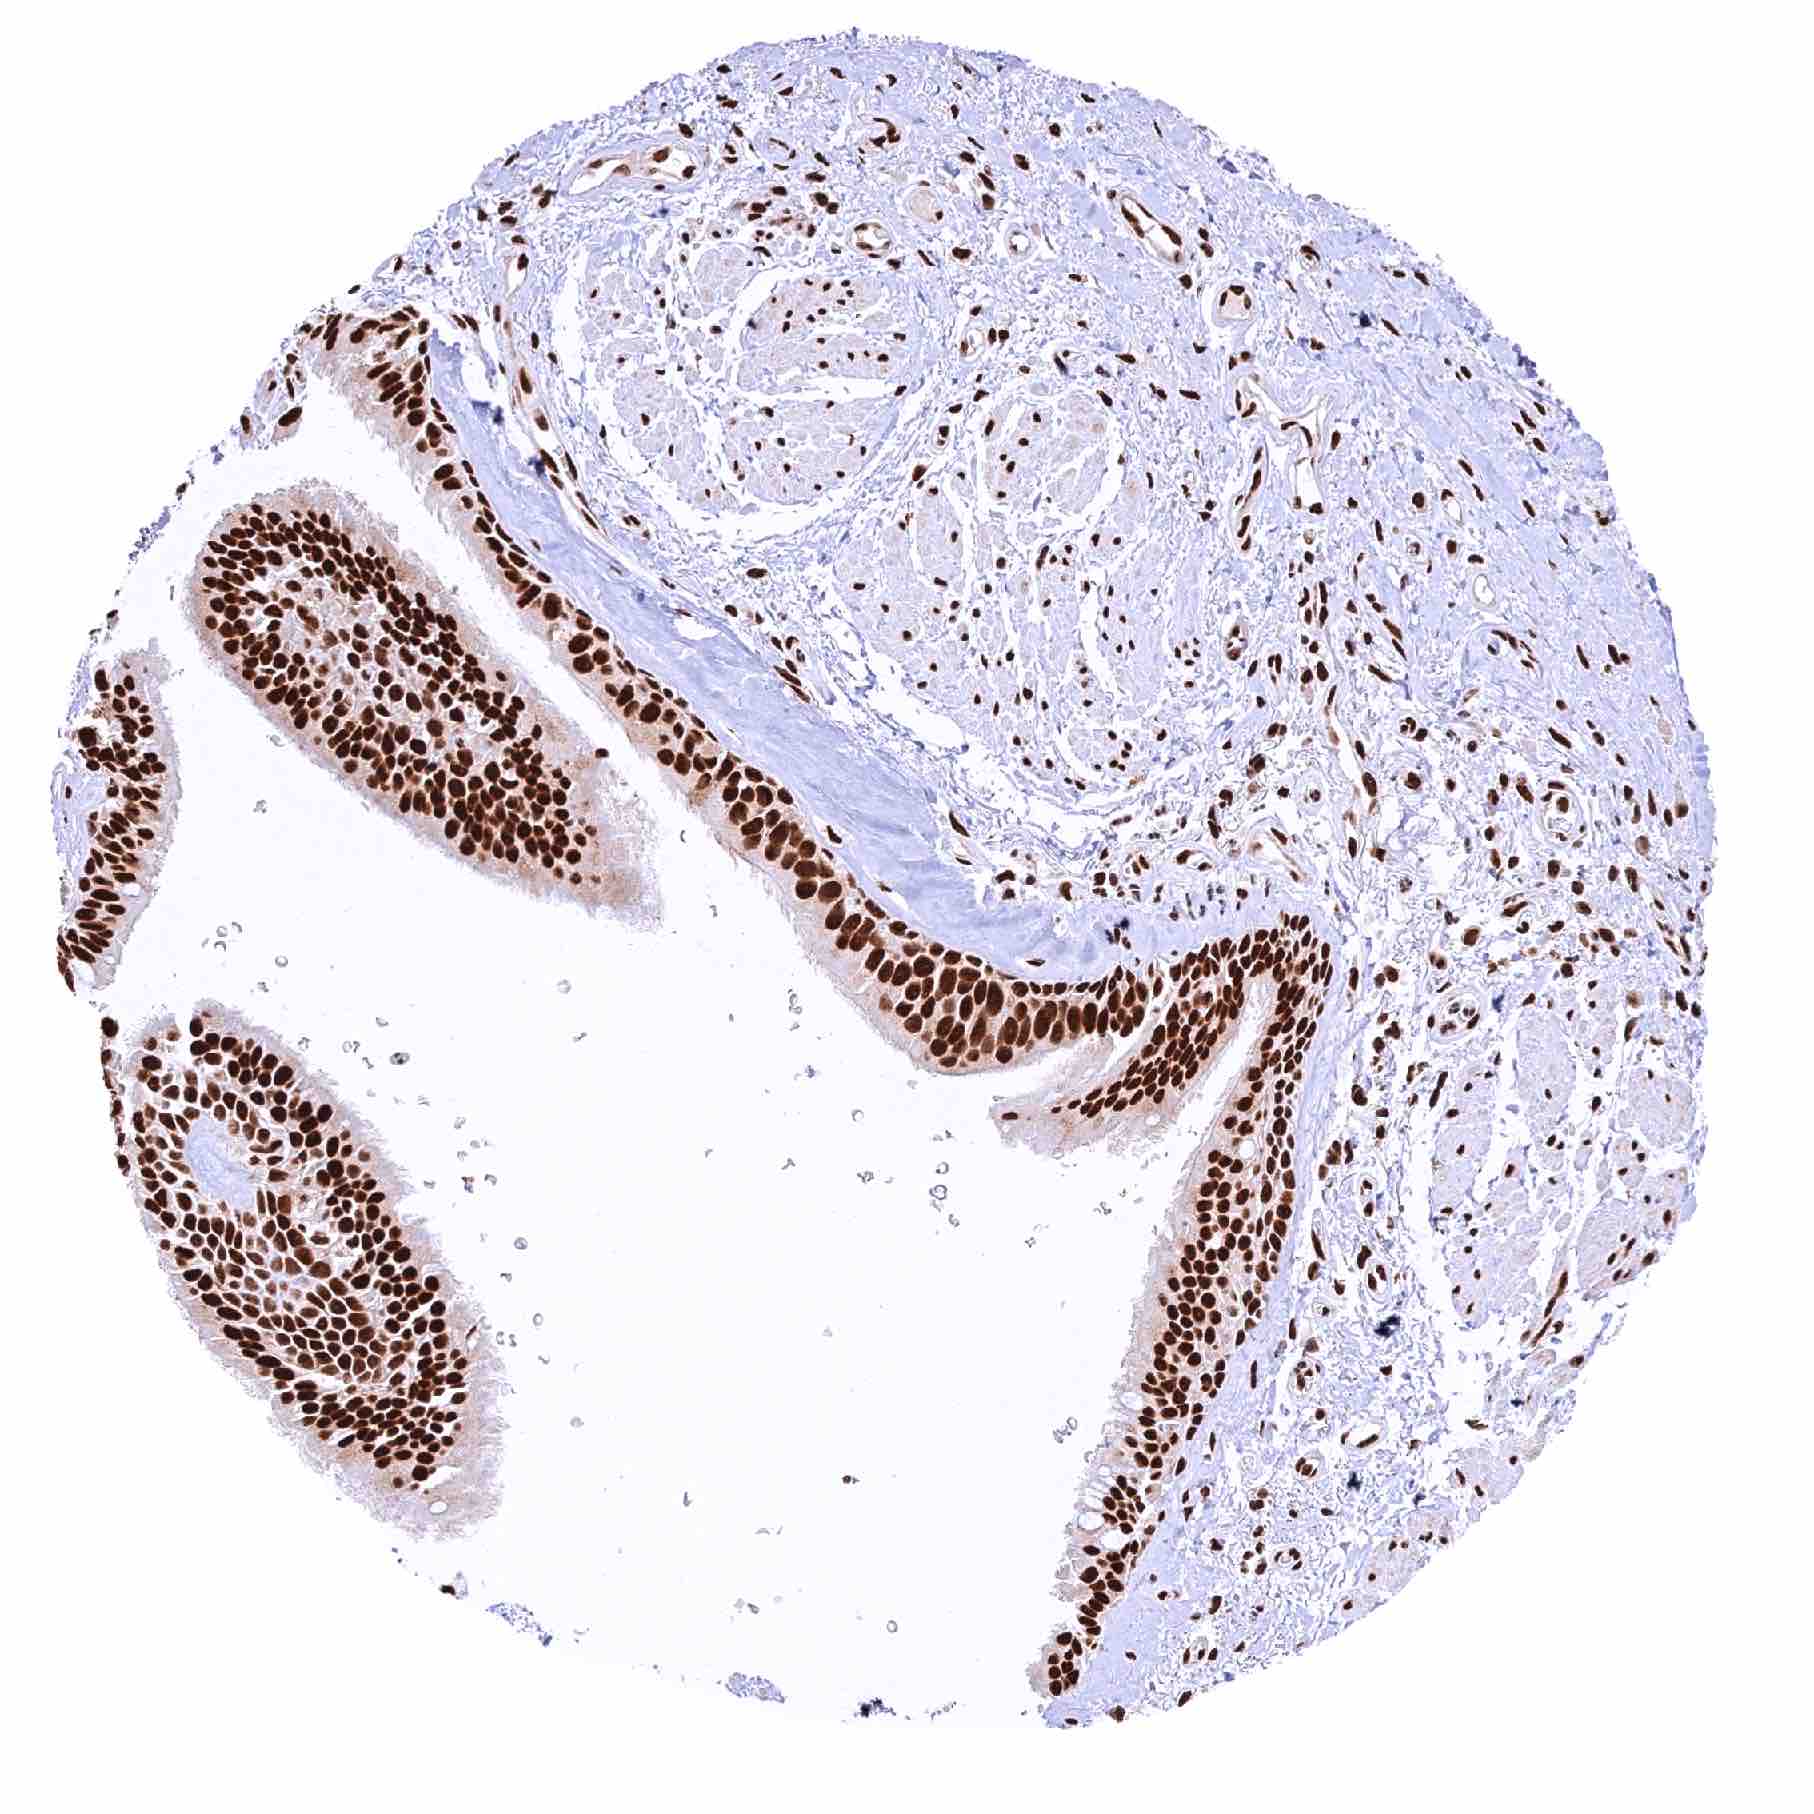

Urinary bladder, urothelium – Strong nuclear MRE11 staining of all cells